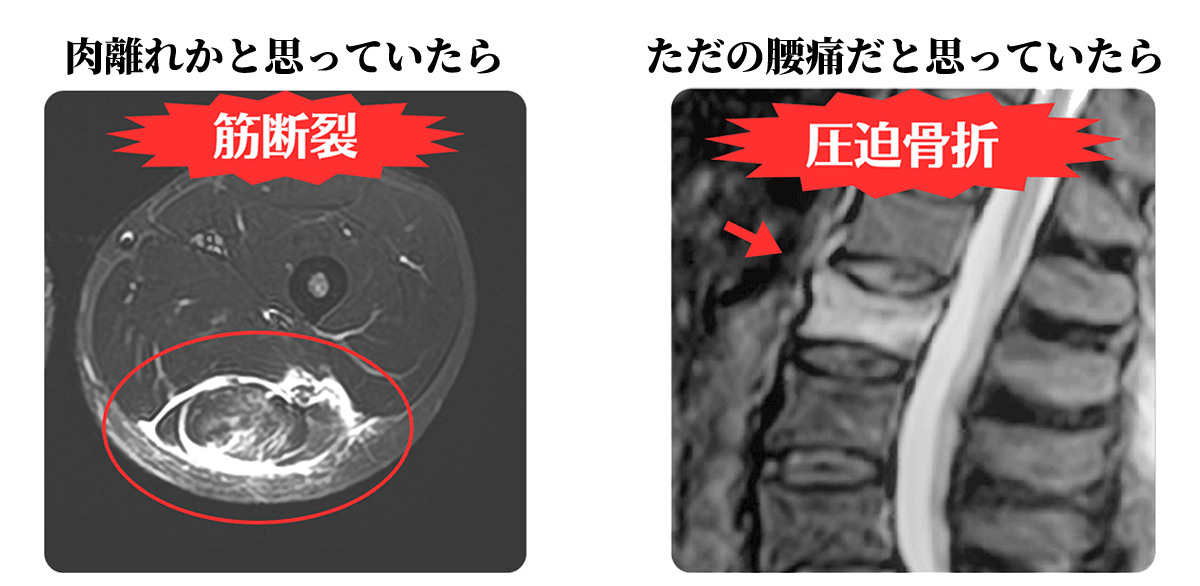

炎症、出血、細菌感染、隠れた腫瘍などを発見することができる!

炎症、出血、腫瘍、水腫(関節に水が溜まること)の有無など、組織の微細な変化(性状)を知ることができます。

原因不明の痛み等に対し、その痛みが炎症によるものなのか、損傷によるものなのかを判断できるため、痛みの真の原因を特定し適切な治療の選択が可能となります。